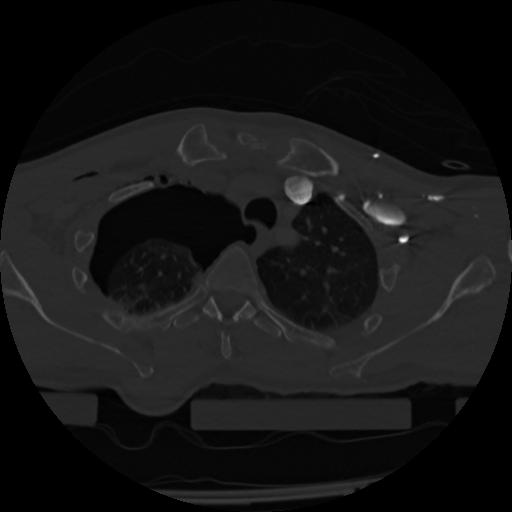

22 ANGIO,CE,Vol,0.5,ANGIO,,